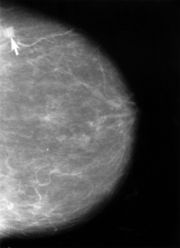

In der Mammographie einer dichten Brust ist das Karzinom kaum zu erkennen

Die Mammographie ist bei Frauen mit dichtem Drüsengewebe in ihrer Aussagekraft begrenzt. Bei extrem dichtem Gewebe werden etwa 50 % der Brusttumoren mammographisch nicht entdeckt. Dies betrifft in erster Linie jüngere Frauen. Frauen mit dichtem Gewebe im Mammogramm wird daher der Einsatz eines zweiten Untersuchungsverfahrens (in der Regel Sonographie, im Einzelfall auch Kernspin-Mammographie) empfohlen.